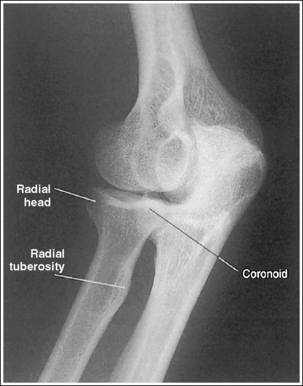

External AP oblique projection: The capitulum-radial joint is open, and the radial head articulating surface is not demonstrated.

Internal AP oblique projection: The trochlea-coronoid process joint is open, and the coronoid process articulating surface is not demonstrated.

The elbow has been internally rotated 45 degrees. The coronoid process, the trochlear notch, and the medial aspect of the trochlea are demonstrated in profile. The trochlear-coronoid process articulation is open, and the radial head and neck are superimposed over the ulna.

• An accurately positioned internally rotated AP oblique elbow projection is obtained by placing the arm in an AP elbow projection and then internally rotating the hand and humerus until the humeral epicondyles are at a 45-degree angle to the IR (Figure 4-74). When the elbow obliquity is correct, the coronoid process is demonstrated in profile and the radial head and tuberosity are superimposed over the ulna. If the humeral epicondyles are at less than 45 degrees of obliquity, the radial head is demonstrated lateral to the coronoid process and does not entirely superimpose the ulna (see Image 83). If the humeral epicondyles are at more than 45 degrees of obliquity, the radial head is partially visualized anterior to the coronoid process (see Image 84).

The elbow has been externally rotated 45 degrees. The capitulum and radial tuberosity are demonstrated in profile, the radial head, neck, and tuberosity are visualized without superimposing the ulna, and the radioulnar articulation is demonstrated.

• Accurate positioning for an externally rotated AP oblique elbow projection is achieved by positioning the arm in an AP projection and then externally rotating the humerus and forearm until the humeral epicondyles form a 45-degree angle with the IR (Figure 4-75). This positioning rotates the radius away from the ulna, demonstrating it without superimposition. If the humeral epicondyles are at less than 45 degrees of obliquity, the radial head and tuberosity still partially superimpose the ulna (see Image 85). If the humeral epicondyles are at more than 45 degrees of obliquity, the coronoid process is partially superimposed over the radial head, and the radial neck and tuberosity are free of superimposition; the radial tuberosity is no longer in profile (see Image 86).